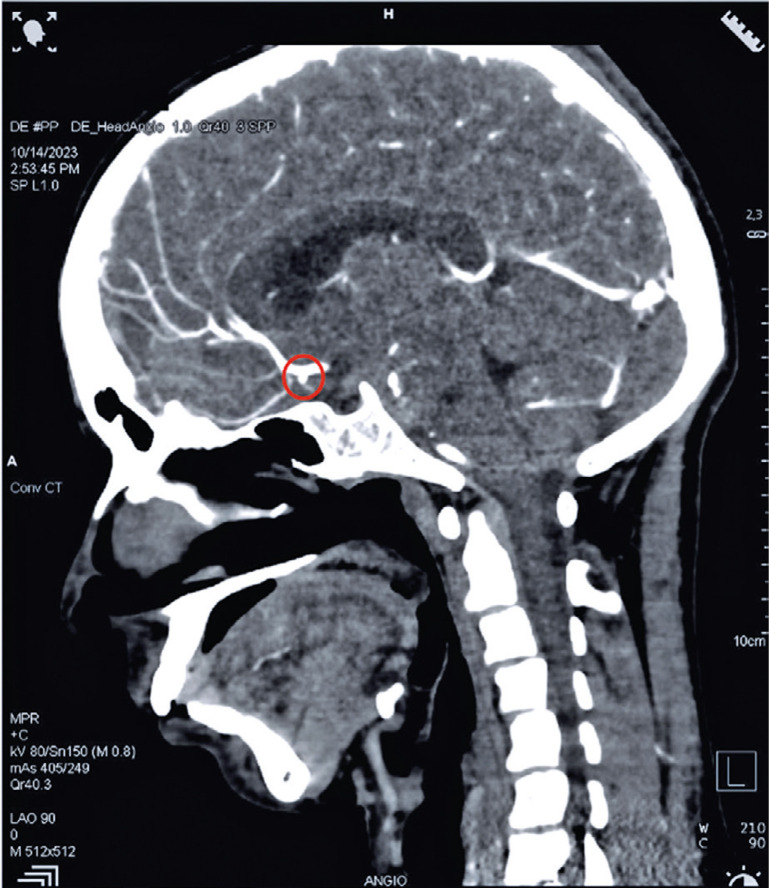

登革热是一种由黄热病病毒属成员引起的病媒传播急性发热性疾病,在全球的发病率急剧上升。登革热的神经系统并发症从 2.63%到 40%不等,蛛网膜下腔出血是一种罕见但重要的表现。嗜血细胞淋巴组织细胞增多症是一种危及生命的高炎症综合征,有时继发于登革热等感染。本报告介绍了一例严重登革热伴蛛网膜下腔出血和嗜血细胞淋巴组织细胞增多症的罕见病例。一名 19 岁男性患者因发热和肌痛就诊 7 天,随后出现剧烈头痛和呕吐。初步检查发现患者有高热、肝脾肿大和全血细胞减少。腰椎穿刺经计算机断层扫描确认,显示费舍尔2级蛛网膜下腔出血,左前冠状动脉和前交通动脉交界处有一个小动脉瘤。根据 2004 年的标准,继发性嗜血细胞淋巴组织细胞增多症被诊断为炎症指标升高、高甘油三酯血症和高铁蛋白血症。患者接受了静脉输液、渗透性利尿剂、抗癫痫药、类固醇和尼莫地平等保守治疗。患者的临床症状有所改善,并于第 11 天出院。孤立的蛛网膜下腔出血在登革热中很少见。嗜血细胞性淋巴组织细胞增多症的高炎症状态往往因症状不特异而被忽视,它可导致动脉瘤形成和破裂。对于伴有神经系统并发症的重症登革热患者,持续发热、全血细胞减少和高铁蛋白血症应引起对嗜血细胞淋巴组织细胞增多症的怀疑。对于严重登革热并发颅内出血的患者,临床医生应继续警惕嗜血细胞淋巴组织细胞增多症,以降低相关的发病率和死亡率。

Dengue, a vector-borne acute febrile illness caused by members of the Flavivirus genus, has dramatically increased its occurrence worldwide. Neurological complications of dengue range from 2.63 to 40%, and subarachnoid hemorrhage is a rare, but significant manifestation. Hemophagocytic lymphohistiocytosis is a life-threatening hyperinflammatory syndrome, sometimes secondary to infections such as dengue. This report presents a rare case of severe dengue with subarachnoid hemorrhage and hemophagocytic lymphohistiocytosis. A 19-year-old male presented with a 7-day history of fever and myalgia, followed by severe headache and vomiting. Initial examination revealed high fever, hepatosplenomegaly, and pancytopenia. Lumbar puncture confirmed via computed tomography showed a Fisher Grade 2 subarachnoid hemorrhage with a small aneurysm at the junction of the left anterior coronary and anterior communicating arteries. Secondary hemophagocytic lymphohistiocytosis was diagnosed based on the criteria from 2004, with elevated inflammatory markers, hypertriglyceridemia, and hyperferritinemia. The patient was treated conservatively with intravenous fluids, osmotic diuretics, antiepileptics, steroids, and nimodipine. The patient showed clinical improvement and was discharged on the 11th day. Isolated subarachnoid hemorrhage is rare in dengue. The hyperinflammatory state in hemophagocytic lymphohistiocytosis, which is often overlooked due to nonspecific symptoms, can lead to aneurysm formation and rupture. Persistent fever, cytopenia, and hyperferritinemia should raise suspicion of hemophagocytic lymphohistiocytosis in cases of severe dengue with neurological complications. In patients with severe dengue and intracranial hemorrhage, clinicians should remain cautious for hemophagocytic lymphohistiocytosis to reduce the associated morbidity and mortality.